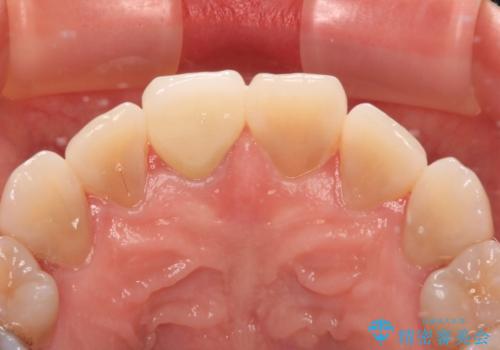

速やかに仮歯に交換し、オールセラミッククラウンにて補綴することとしました。

神経組織が健全な状態で残っている歯であったため、1ヶ月かからずに治療を終えることができました。